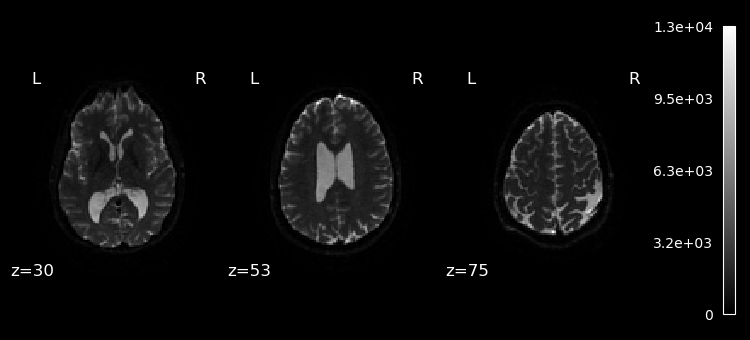

Lets plot the first 10 volumes.

%matplotlib inline

from nilearn import image

from nilearn.plotting import plot_epi

selected_volumes = image.index_img(dwi, slice(0, 10))

for img in image.iter_img(selected_volumes):

plot_epi(img, display_mode="z", cut_coords=(30, 53, 75), cmap="gray")